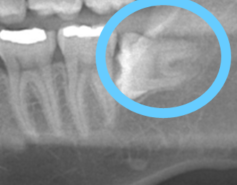

ゆめ森でレントゲンを撮影し画像を見せてもらったときに発覚!

しかも、歯科ドクターが一番苦労するという下あごの親知らずで、かつ手前の歯に対して真横に生えてくるパターンでした(^^💦あら

残してもいいけれど、私の場合レントゲン画像の様に、

真横に生えてしまっているので、これがどんどん前に出てきてしまったら、前に生えている歯が押されてしまい、歯並びがずれてしまうかもしれない事、

そしてすでに隣接している歯との間に小さく虫歯ができてしまっているようでした。